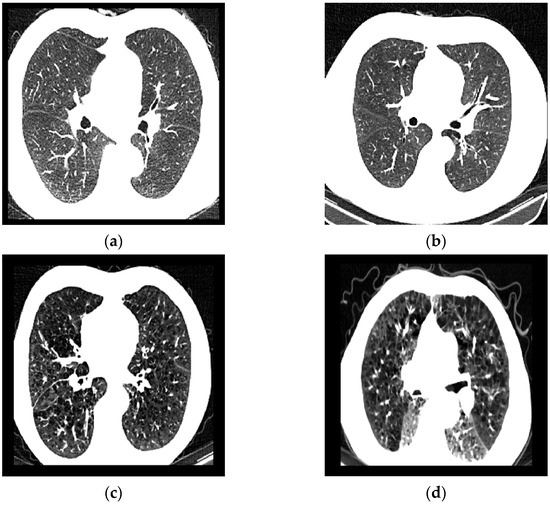

ILD-Slider: A Parameter-Efficient Model for Identifying Progressive Fibrosing Interstitial Lung Disease from Chest CT Slices

by Jiahao Zhang, Shoya Wada, Kento Sugimoto, Takayuki Niitsu, Kiyoharu Fukushima, Hiroshi Kida, Bowen Wang, Shozo Konishi, Katsuki Okada, Yuta Nakashima and Toshihiro Takeda

J. Imaging 2025, 11(10), 353; https://doi.org/10.3390/jimaging11100353 - 9 Oct 2025

Progressive Fibrosing Interstitial Lung Disease (PF-ILD) is a severe phenotype of Interstitial Lung Disease (ILD) with a poor prognosis, typically requiring prolonged clinical observation and multiple CT examinations for diagnosis. Such requirements delay early detection and treatment initiation. To enable earlier identification of [...] Read more.

Progressive Fibrosing Interstitial Lung Disease (PF-ILD) is a severe phenotype of Interstitial Lung Disease (ILD) with a poor prognosis, typically requiring prolonged clinical observation and multiple CT examinations for diagnosis. Such requirements delay early detection and treatment initiation. To enable earlier identification of PF-ILD, we propose ILD-Slider, a parameter-efficient and lightweight deep learning framework that enables accurate PF-ILD identification from a limited number of CT slices. ILD-Slider introduces anatomy-based position markers (PMs) to guide the selection of representative slices (RSs). A PM extractor, trained via a multi-class classification model, achieves high PM detection accuracy despite severe class imbalance by leveraging a peak slice mining (PSM)-based strategy. Using the PM extractor, we automatically select three, five, or nine RSs per case, substantially reducing computational cost while maintaining diagnostic accuracy. The selected RSs are then processed by a slice-level 3D Adapter (Slider) for PF-ILD identification. Experiments on 613 cases from The University of Osaka Hospital (UOH) and the National Hospital Organization Osaka Toneyama Medical Center (OTMC) demonstrate the effectiveness of ILD-Slider, achieving an AUPRC of 0.790 (AUROC 0.847) using only five automatically extracted RSs. ILD-Slider further validates the feasibility of diagnosing PF-ILD from non-contiguous slices, which is particularly valuable for real-world and public datasets where contiguous volumes are often unavailable. These results highlight ILD-Slider as a practical and efficient solution for early PF-ILD identification. Full article